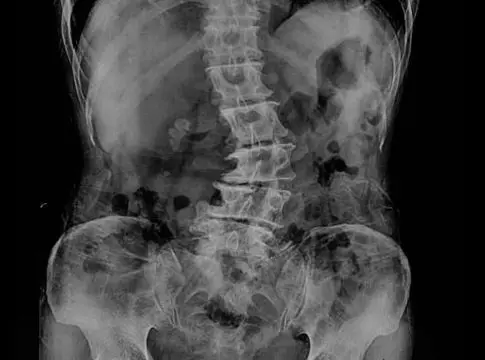

Para diagnosticar la escoliosis lumbar, los profesionales de la unidad médica Biziondo pueden llevar a cabo un examen físico, una radiografía de la columna vertebral o una resonancia magnética. En ese sentido, lo ideal es obtener un diagnóstico temprano mediante un examen médico, con la finalidad de prevenir la aparición de complicaciones a largo plazo.